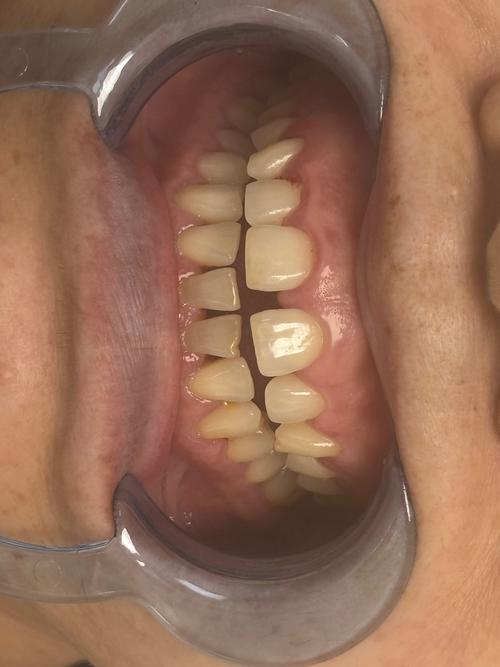

(图片来源网络,侵删)- 原因: 拔牙后未及时修复(种植、镶牙、活动假牙),邻牙会向缺隙倾斜移位,对颌牙伸长,导致邻牙与邻牙之间、邻牙与对颌牙之间出现牙缝。